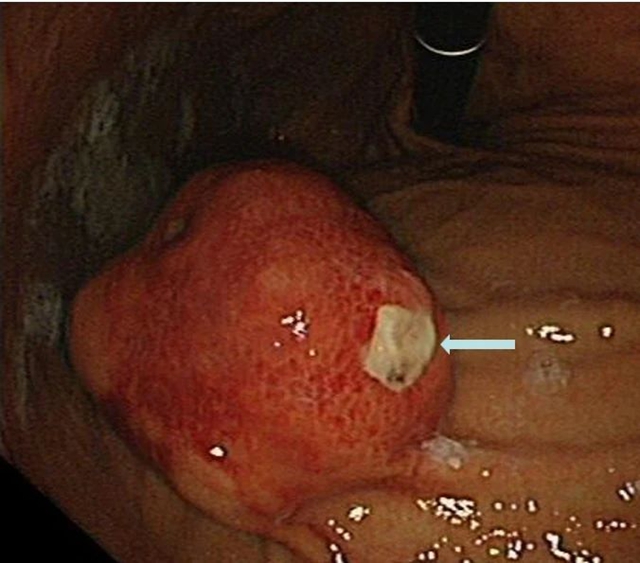

胃内大型黏膜下肿物破溃出现,箭头处为溃疡处

今年春节前夕,72岁的李婆婆被送入西南医科大学附属医院急诊科就诊时,呈休克状态,伴有呕血、黑便与贫血等症状。胃镜检查发现,她是因胃黏膜下肿物破溃出血才导致出现系列症状。

“切掉肿物,出血就会停止。”西南医科大学附属医院消化内科副主任汤小伟副教授介绍,李婆婆体内胃肿物直径约4厘米,邻近肝脏、胰腺等重要脏器。这类肿物常隐藏于黏膜之下,早期没有明显症状,倘若未能及时发现,就会悄悄增大导致疼痛、出血、梗阻,甚至危及生命。